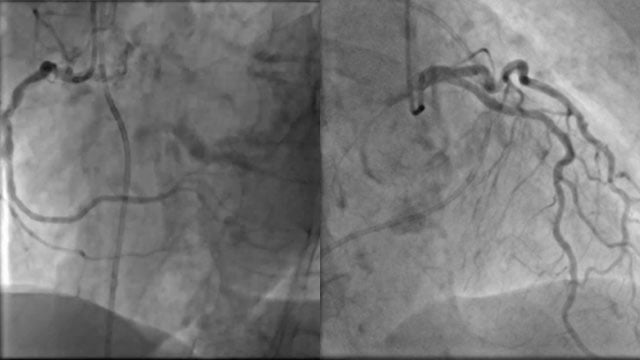

An 85-year-old woman presents with exertional dyspnea and angina, alongside severe paradoxical low-flow, low-gradient aortic stenosis, marked mitral and tricuspid valve disease, and two-vessel coronary artery disease. Frailty markers and hostile pelvic anatomy further complicate her profile.